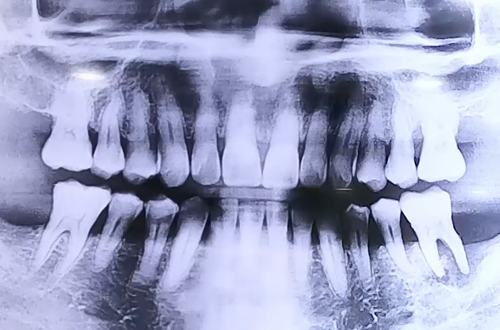

BEFORE

왼쪽 어금니에 지속적인 통증을 느끼고 내원해주셨던 환자분입니다.

엑스레이를 찍어보니 왼쪽 위아래 어금니가 흔들리고 있었고, 주위 잇몸이 많이 약해지고 염증도 있는 상황이었습니다.

약해진 잇몸 탓에 치아가 흔들리니 음식이 잘 씹어지지 않았던 것이죠.

잇몸의 높이가 내려가면서 그 부분에 음식물이 더 잘 끼면서 염증이 잘 생기게 되는데, 환자분도 그런 케이스를 보이고 계셨습니다.

때문에 위아래 약해진 치아를 빼고 임플란트 진행을 계획하였는데요.